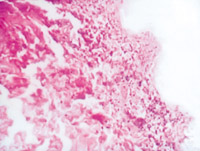

5-2-1 傷后第1天,表皮凝固性壞死,真皮淺層膠原纖維變性  HE×100